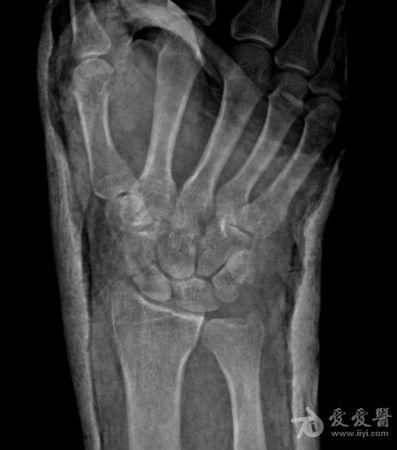

右手舟状骨骨折4个月

右手舟状骨骨折四个月,一直石膏保守治疗,拍片如下,请问,现在是手术治疗好还是继续保守治疗?